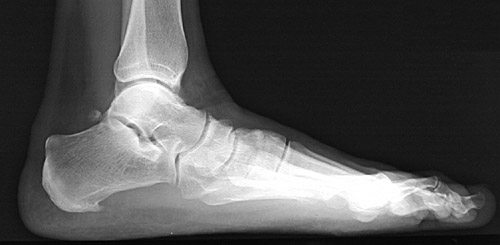

This is a lateral radiograph of the foot demonstrating the calcaneus and talus and navicular and cuboid and cuneiforms and metatarsals and phalanges.